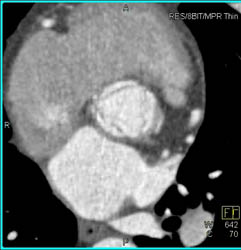

Sa Nodal Branch Off Right Coronary Artery (RCA)